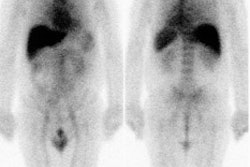

|

Rb-82 rest perfusion examination |